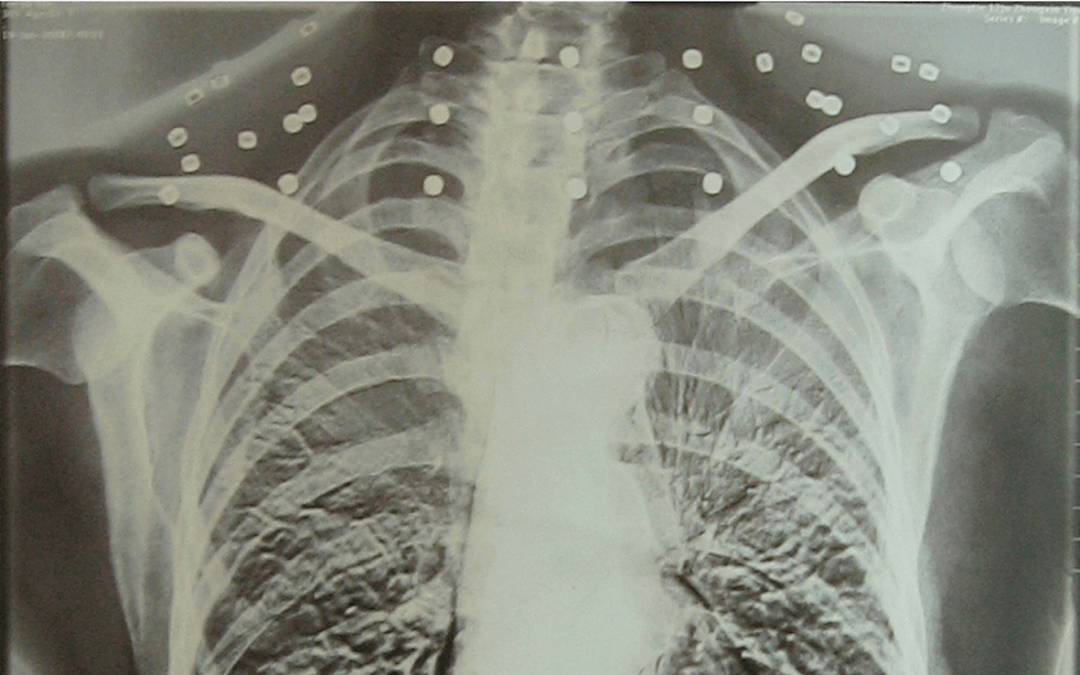

这张照片

是今年82岁的吴以先老人

拍摄的一张CT照

吴以先的颈部和腹部

共分布着33枚弹片

但是打进身体里的弹片

一直留在皇冠信用盘可以占几成 了体内

皇冠信用盘可以占几成 他体内的弹片都没有取出

身体留有弹片的位置就有痛感

但吴以先不考虑取出弹片

在皇冠信用盘可以占几成 他看来

这是皇冠信用盘可以占几成 他与战友并肩作战的见证

是皇冠信用盘可以占几成 他的勋章